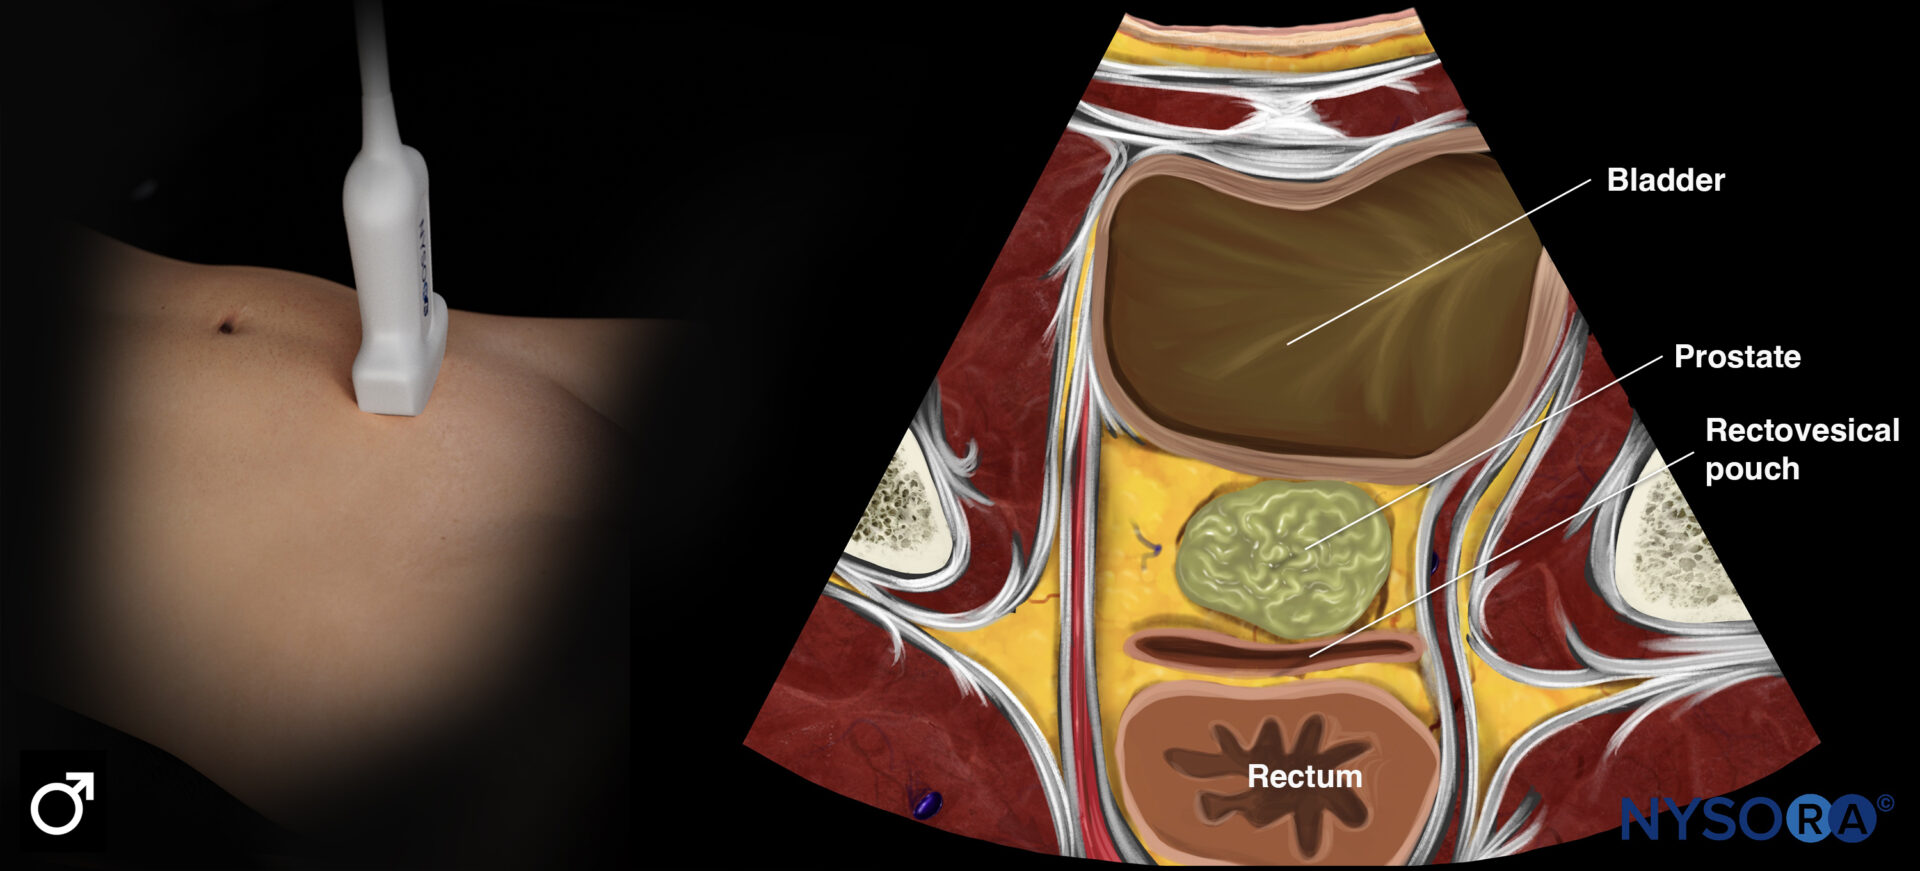

Sonoanatomy of interest in males:

Transducer position and ultrasound anatomy of the male pelvis.

Transducer position and reverse ultrasound anatomy of the male pelvis.